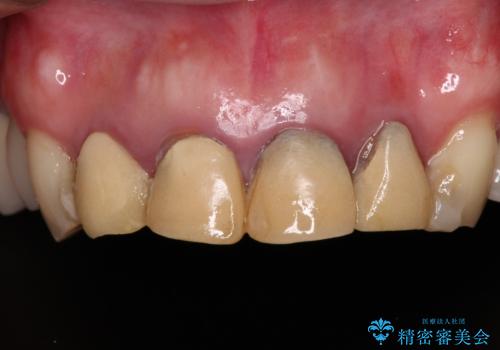

- 仮歯装着後に放置してしまい、恥ずかしいとのことで来院された患者様です。

仮歯が不適合で歯肉が腫脹していたため、しっかりと調整した新しい仮歯にして腫れを改善した上で、オールセラミッククラウンにて補綴することとしました。